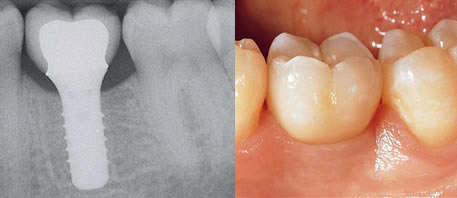

Before Dental Implant

dental implants northern ireland

After Dental Implant